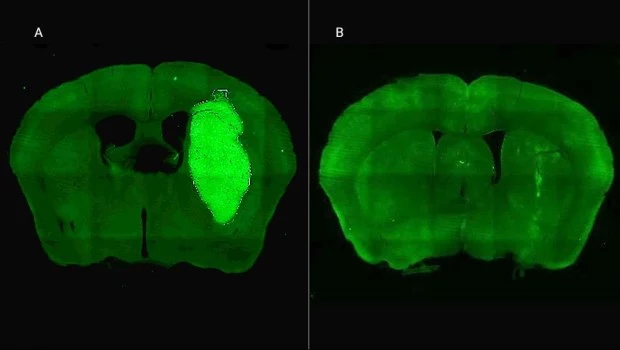

En estudios in vivo, el equipo liderado por Candolfi utilizó ratones inoculados en el cerebro con neuroesferas que contienen lesiones características de los tumores humanos que fueron desarrollados por el laboratorio de la científica argentina y colaboradora del estudio María Castro en la Universidad de Michigan, en Estados Unidos. Para tratar los tumores in vivo, los equipos de Candolfi y de la también científica del CONICET Flavia Zanetti, del Instituto de Ciencia y Tecnología César Milstein (CONICET- Fundación Pablo Cassará), desarrollaron un vector adenoviral que expresa la molécula o péptido P60 al interior de las células tumorales.

“Esta estrategia permite la expresión sostenida de P60 en la zona del tumor, facilitando la terapia y reduciendo la probabilidad de efectos colaterales sistémicos. Una inyección intratumoral del vector inhibió el crecimiento del tumor y mejoró notablemente la respuesta a la quimioterapia, llevando a la erradicación del tumor y sobrevida a largo plazo en un tercio de los ratones con tratamiento combinado”, afirma Candolfi. Y agrega: “No observamos efectos neurotóxicos con ninguno de los tratamientos empleados, por lo tanto, esta estrategia tendría buen perfil de seguridad para tratar estos tumores”.